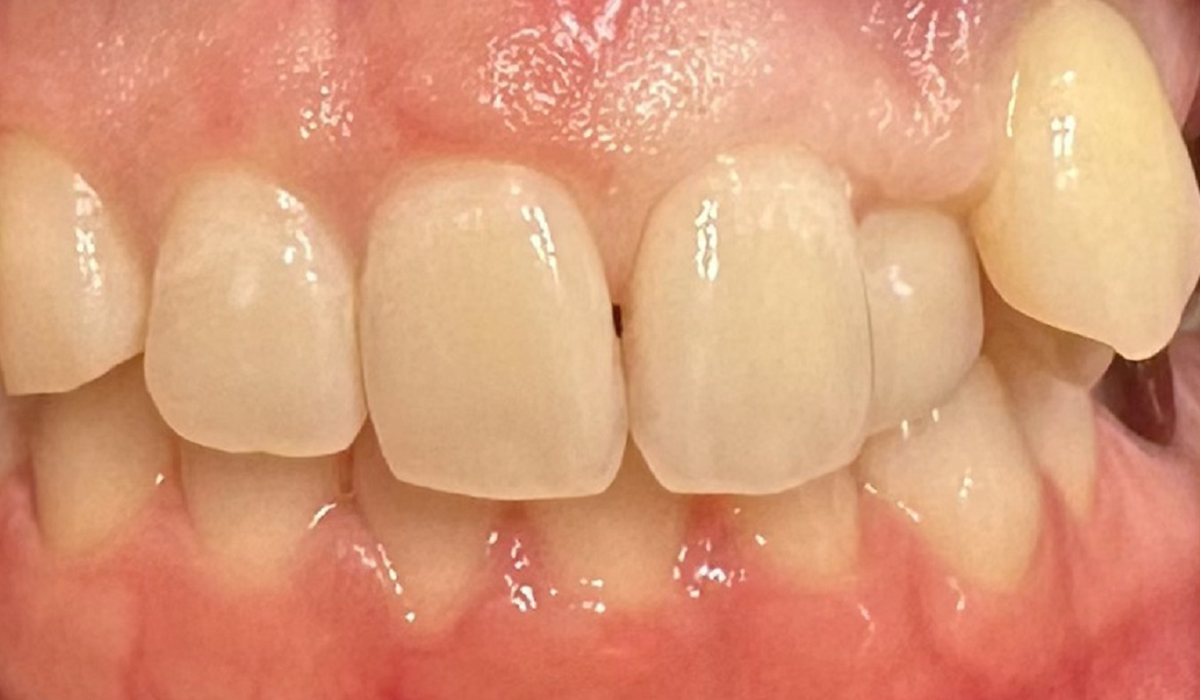

- 前歯のすきっ歯

歯と歯の間の隙間をダイレクトボンディングで自然な見た目に修復しています。